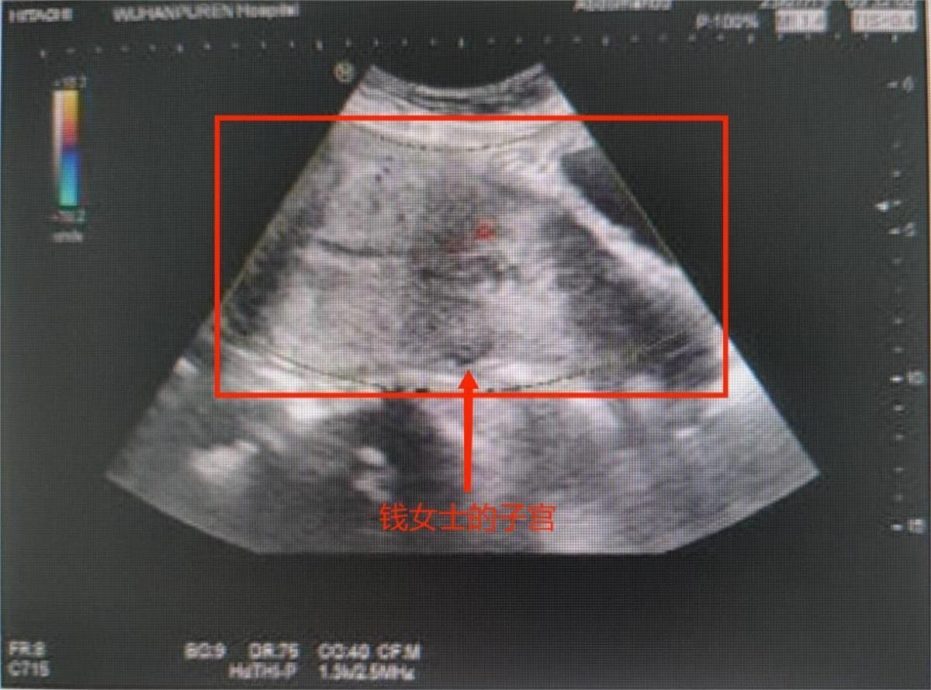

吓坏了的钱女急忙赶到武汉市普仁医院就医,医生第一时间为她进行了相关检查,发现钱女竟然是流产了,而那个掉出来的“肉团”竟是一个已满24周的胎儿。